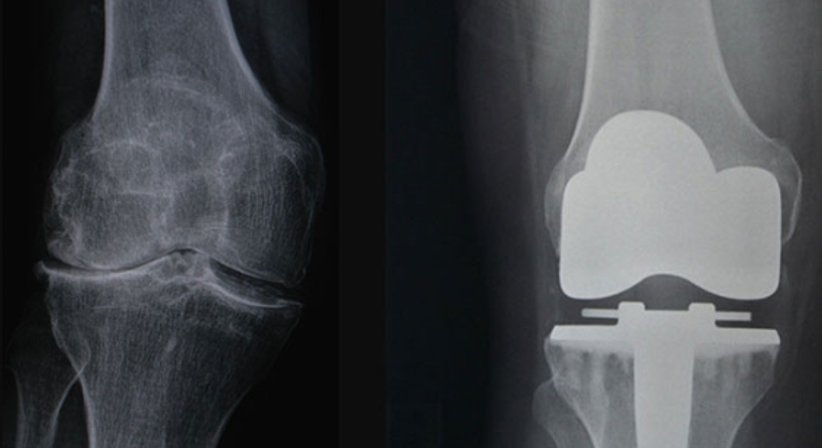

Totalendoprothese

Ist das ganze Kniegelenk von einer Abnützung (Arthrose) betroffen, wird eine Totalendoprothese eingesetzt. Mit diesem sogenannten Oberflächenersatz wird nur der abgenützte und erkrankte Gelenkknorpel ersetzt. Die wichtigen Bänder des Kniegelenks (unter anderem das innere und äußere Seitenband sowie das hintere Kreuzband) bleiben erhalten, um die nötige Stabilität zu gewährleisten.

Es kommen ausschließlich Prothesenmodelle zum Einsatz, die sich auch in Langzeitstudien über 15 bis 20 Jahre bewährt haben und eine hervorragende Haltbarkeit aufweisen.